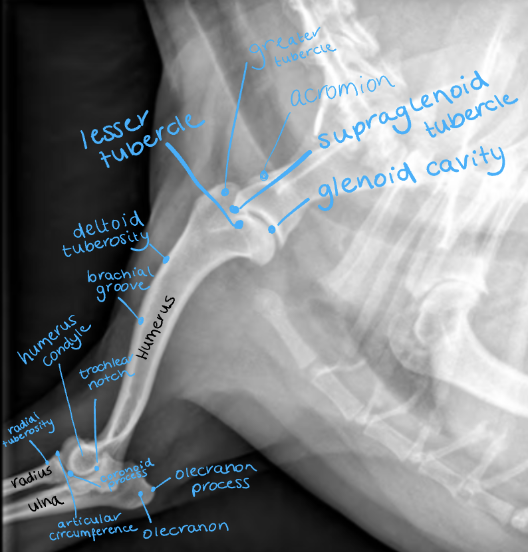

Label the image

A